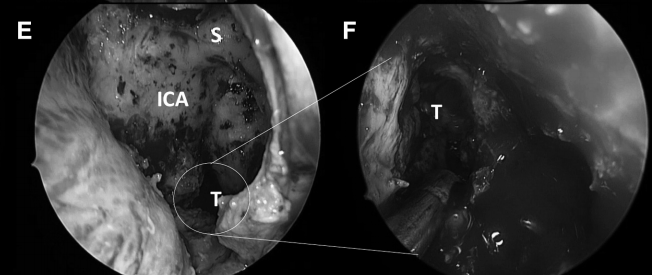

▼从该切口可暴露右颈静脉结节区域的充足手术通道(图8E和F)。

▼然后肿瘤被切除。在图8G中,可见肿瘤基底部暴露,并且颈静脉孔神经部组织可以通过组织质地来区分。

CD,斜坡凹陷;S,蝶鞍;SR,蝶嘴;T,肿瘤。